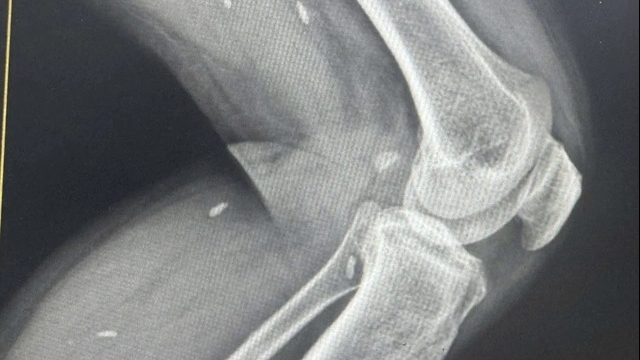

Ngay sau khi tiếp nhận, các bác sĩ đã cấp cứu hồi sức và đưa bệnh nhân đi thực hiện các xét nghiệm và các cận lâm sàng cần thiết. Kết quả chụp cho thấy bệnh nhân bị gãy vững đốt sống T12 có mảnh xương vỡ chèn ép vào tuỷ sống. Tiến hành hội chẩn liên khoa, nhận định với trường hợp tổn thương như vậy, nếu không can thiệp sớm thì khả năng phục hồi sẽ rất thấp.

Đến 21h cùng ngày, kíp phẫu thuật của bệnh viện đã sẵn sàng. Bệnh nhân được chuyển thẳng lên phòng mổ để xử lý tổn thương. Tại đây, các bác sĩ đã phẫu thuật cố định cột sống bằng nẹp vít, mở cung sau D12 giải ép tủy, đặt 2 thanh rod cố định, nắn chỉnh lại mảnh xương vỡ gây chèn ép. 6h sau phẫu thuật, 2 chân bệnh nhân đã phục hồi vận động. Bệnh nhân đã tự co và nâng được chân khỏi giường.